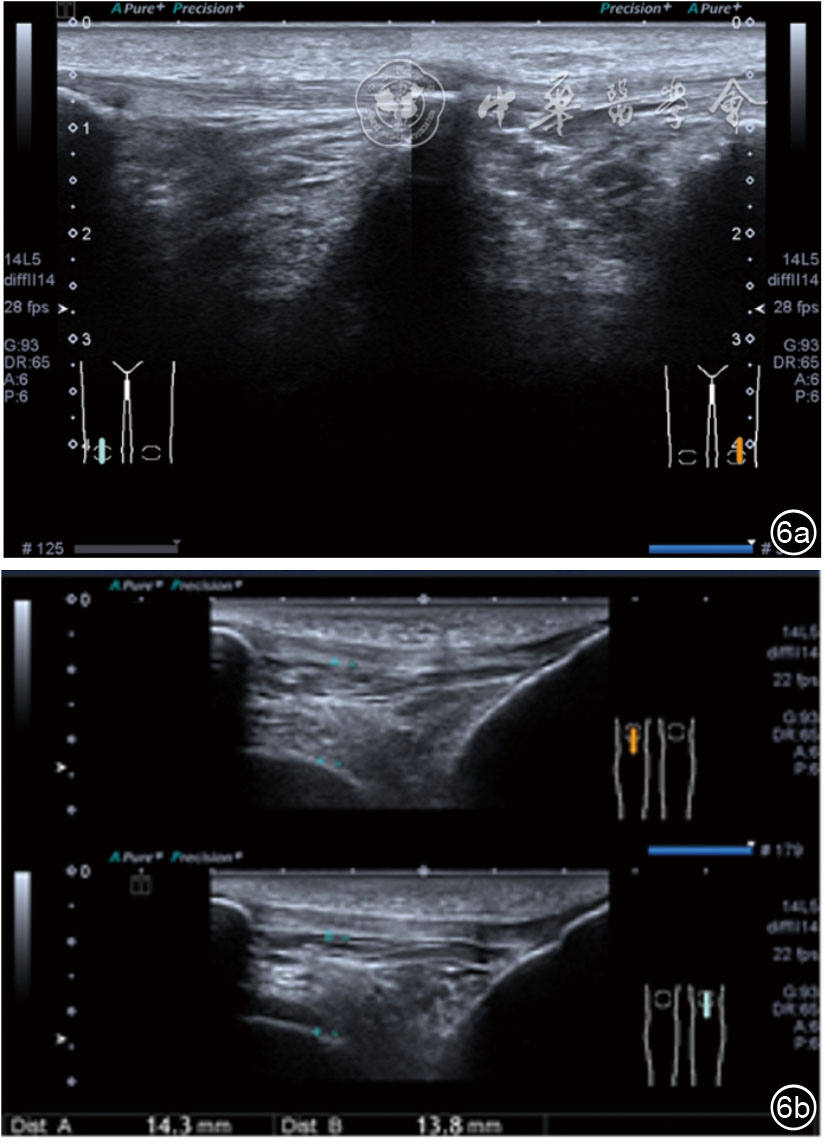

患者采取侧卧位,患肢在上,屈膝20°。应用10~18 MHz高频线阵探头,扫查深度1~3 mm。长轴和短轴结合双侧对比扫查。超声影像学所见:短轴可见卡压腓总神经近端增粗,面积增大;长轴可见腓总神经卡压处变细,其近侧肿胀、回声减低,而在卡压远侧则表现正常(图35);一些受压严重者可以出现神经周围积液,卡压神经部位的筋膜增厚(图36);受压神经内血流增加对临床诊断意义更大(图37);探头在病变神经处加压常可引起神经刺激症状。腓总神经支配的肌肉有失神经支配改变,表现为肌肉回声增高和肌肉萎缩(图38)。

图35 超声短轴可见卡压腓总神经近端增粗,面积增大;长轴可见腓总神经卡压处变细,其近侧肿胀、回声减低